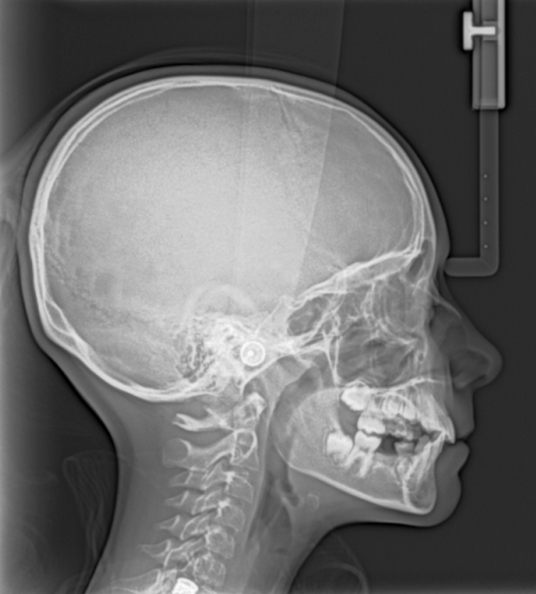

Ceph Upgradeable - "One-Shot" cephalometry captures picture-perfect cephalometric images in just over a second. Cephalometric exams include: lateral, frontal (AP/PA), submento-vertex, and carpus in the following size choices: 30 x 30, 24 x 30, 24 x 24, 18 x 24, 18 x 18 cm.